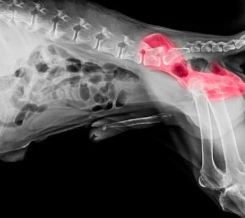

4) 진단 방법

보통 동물병원에서는 엑스레이(X-ray), 초음파, MRI 등을 통해 관절 구조를 확인합니다. 특히 전신마취 후 촬영하는 방사선 사진이 확진에 많이 활용됩니다.